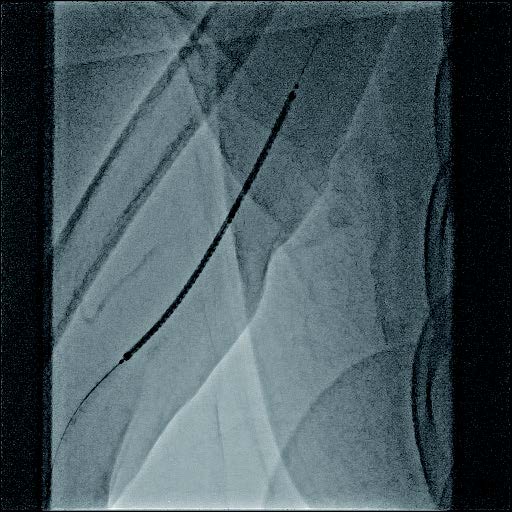

- シース:7 Fr シース

- ガイドワイヤー:0.018 inch (サポートタイプ)

- PTA バルーンカテーテル:径6 mm×長100 mm

- ステントグラフト:バイアバーン® ステントグラフト 径7 mm×長100 mm

バイアバーン® ステントグラフト留置の手技については、当施設では概ね毎回同じ手技を実施している。ステントグラフトの長さについては病変に依存するが、径については6 mmの人工血管に対して、7 mmのバイアバーン® ステントグラフトを留置している。

また、バイアバーン® ステントグラフトは、位置決めをした後の留置時に移動する事象は自施設で行った症例ではほとんど認めていないが、展開時のstabilityを保つため0.018 inchのサポートワイヤーを用いることが多い。当患者においても、上記手技を行い良好なinitial successを得られた。他症例もほぼ同一の手技で行っているがサイズなどで問題になった症例は、本稿の執筆時点では経験していない。